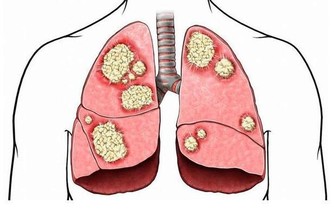

但患了胃潰瘍、十二指腸潰瘍、胃癌或腸癌等疾病也會引起消化道出血引起黑便,患者會伴隨腹痛、腹瀉、噁心、嘔吐等不適症狀。

而體內的濕氣過重,平常活動量比較少,身體過於肥胖的人也容易出現黏液便。患了膽囊結石,胰臟癌或膽管癌之後,導致膽管受到壓迫,也會使腸道裡面的膽紅素數量減少,導致大便變成灰白色。